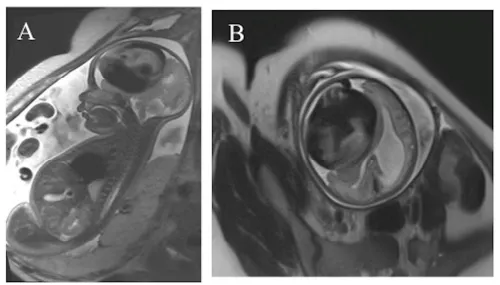

胎儿MRI发现右侧大脑半球巨大血管病变,压迫邻近脑实质,致中线结构向对侧移位,还出现早期梗阻性脑积水(图1A-B)。还好的是,胎儿生命体征稳定,因此医生决定等待胎儿出生后再进行治疗。

图1A-B

当天又进行磁共振血管成像(MRA),显示右侧额叶软脑膜动静脉瘘(PAVF),伴软脑膜静脉瘤样扩张,其内血流湍急,经扩张静脉引流入上矢状窦(图1C-E);病变还压迫同侧脑组织,致局部脑实质萎缩。

图1C-E